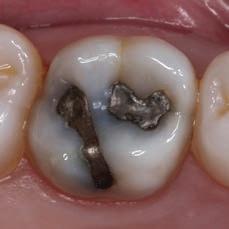

2. Remove old amalgam. Keep caries as a barrier for the time being, in case

DO NOT